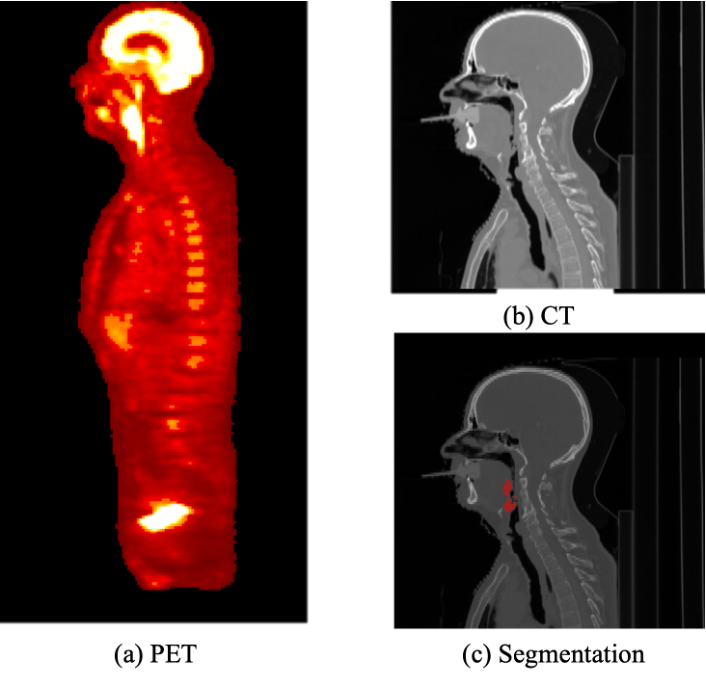

The 5-year survival rate of Head and Neck Cancer (HNC) has not improved over the past decade and one common cause of treatment failure is recurrence. In this paper, we built Cox proportional hazard (CoxPH) models that predict the recurrence free survival (RFS) of oropharyngeal HNC patients. Our models utilise both clinical information and multimodal radiomics features extracted from tumour regions in Computed Tomography (CT) and Positron Emission Tomography (PET). Furthermore, we were one of the first studies to explore the impact of segmentation accuracy on the predictive power of the extracted radiomics features, through under- and over-segmentation study. Our models were trained using the HEad and neCK TumOR (HECKTOR) challenge data, and the best performing model achieved a concordance index (C-index) of 0.74 for the model utilising clinical information and multimodal CT and PET radiomics features, which compares favourably with the model that only used clinical information (C-index of 0.67). Our under- and over-segmentation study confirms that segmentation accuracy affects radiomics extraction, however, it affects PET and CT differently.